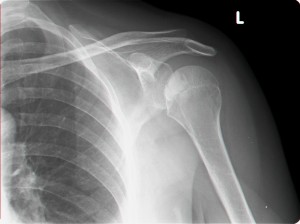

נ.מ לפני טיפול בגלי הלם:

כתף קפואה               טיפול בכתף קפואה